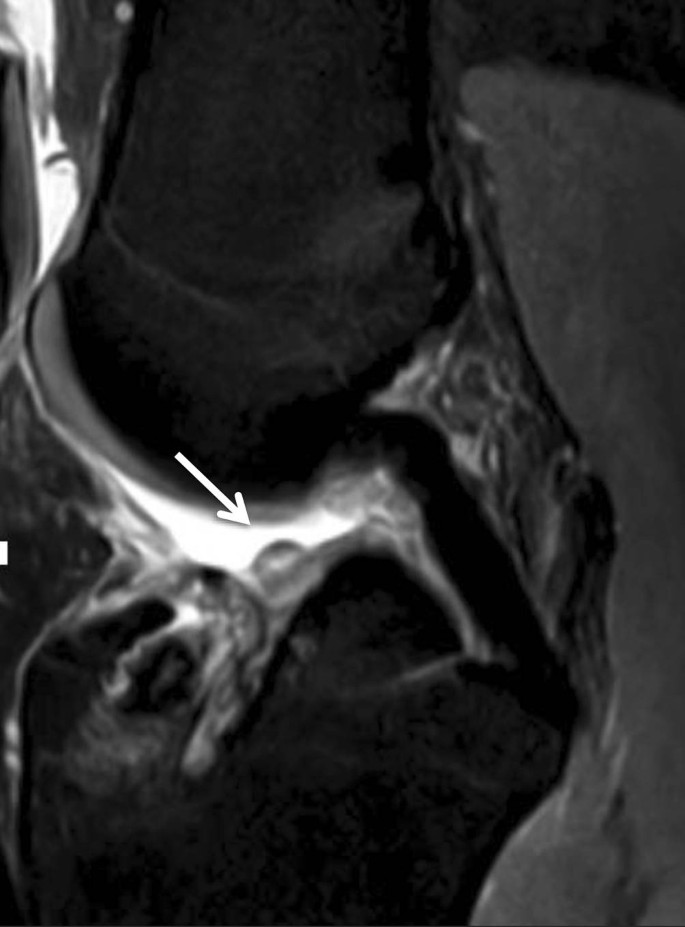

Roof-Impingement

Der Zusammenstoß zwischen den posterioren femoralen Anteilen der VKB-Plastik und dem Femurkondylus im Bereich des femoralen Notch wird als Roof-Impingement bezeichnet (Abb. 9). Ein zu weit anterior angelegter tibialer Bohrkanal führt bei gestrecktem Kniegelenk zum Roof-Impingement. Die VKB-Plastik weist einen gebogenen Verlauf um den anteroinferioren Anteil des Femurkondylendachs (Notch) auf. Typischerweise findet sich eine ödematöse Auftreibung der Plastik, was sich etwa 12 Wochen nach der Notch-Plastik normalisieren kann. Die Notch-Plastik ist eine Knochenentnahme am lateralen Femurkondylus, um den Konflikt zwischen der VKB-Plastik und dem Knochen zu beheben [14].

Abb. 9

figure 9

Roof-Impingement: In der sagittalen STIR(„short tau inversion recovery“)-Sequenz zeigt sich ein bogenförmiger Verlauf der Plastik. Die fokale Signalanhebung der Plastik im mittleren Drittel wird vermutlich durch ein Impingement gegen das Dach der Femurs hervorgerufen (Pfeil)